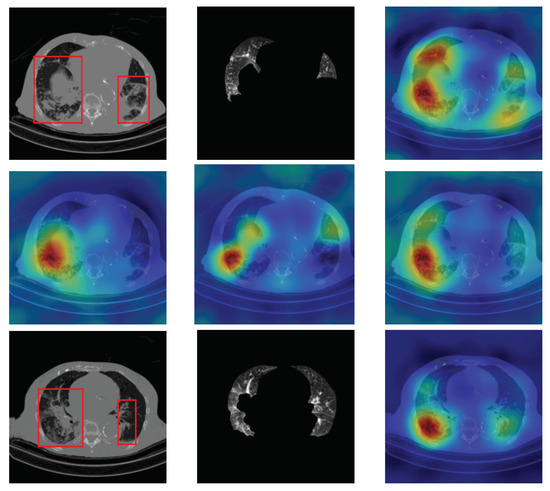

4.5. Heat Map

To have more intuition about the most important lung regions that the CNN architectures consider to classify the slice images, we used the randomized input sampling for explanations (RISE) approach [37]. Figure 13, Figure 14 and Figure 15 consist of two heat map examples of COVID-19, Cap, and normal cases, respectively. In the first example from Figure 13, we notice that despite the lung segmentation being not fully correct (it misses a considerable part of the infected region), the four CNN architectures gave more importance to the infected regions and to the lung regions in general. In the second example from Figure 13, we observe that the lung lobes were precisely segmented, and the heat maps of the four CNN architectures were well defined the infected regions, especially the Wide-Resnet-50 architecture. From both Cap examples in Figure 14, we notice that despite the lung segmentation missing considerable infected parts as well as the lung lobe regions, the heat maps of all CNN architectures give more importance to the infected region and to the lung lobes in general. This proves that the trained CNN architecture is able to define the regions of interest even when the lung lobes segmentation is not good. For the normal slice examples in Figure 15, the trained CNN architectures gave more importance to the lung lobes, especially the lower region, since the infection usually occurs there. The heat maps of COVID-19, Cap, and normal cases prove that the CNN architectures learned precisely where to look to identify the infection from the slice images.

Figure 14.

RISE heat map examples of Cap slice image using the trained multi-tasks CNN architectures (ResneXt-50, Densenet-161, Inception-v3, and Wide-Resnet-50). The first example is shown in the first two rows, where the images represent the input slice image and segmented lung lobes results, followed by the heat maps of ResneXt-50, Densenet-161, Inception-v3, and Wide-Resnet-50, respectively. The second example is in rows 3 and 4.